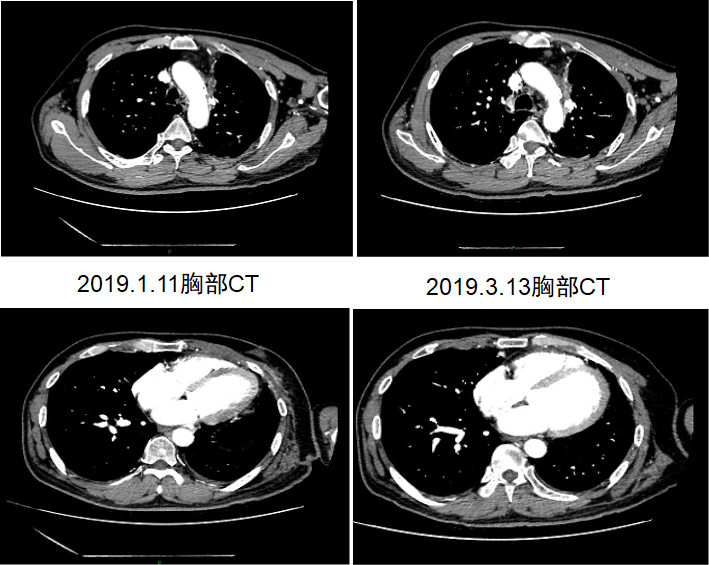

2018年10月16日起,患者接受信迪利单抗(200mg,d1)/安慰剂+吉西他滨(1650mg,d1,d8)+顺铂(122mg,d1)治疗4周期。用药2周期后,于2018年11月28日进行疗效评价为PR(图7)。期间患者出现Ⅱ度骨髓抑制,给予升白细胞等治疗后恢复。4周期治疗结束后,2019年1月12日再次进行疗效评价为PR(图8),治疗期间患者无明显不良反应。1月12日起,患者接受信迪利单抗(200mg,d1)/安慰剂维持治疗,共16周期,末次治疗时间为2020年2月3日,疗效PR(图9),PFS超过15个月,患者生活质量较前明显改善。维持治疗期间,患者每次输注临床用药后均有轻度的皮肤瘙痒症状,2-3天后缓解,考虑1级不良反应。

image013.png

图7.患者入组临床试验治疗2周期后疗效评价为PR

image015.png

图8.患者2019年1月和3月影像学资料

图9.维持治疗期间定期进行疗效评价,患者肿瘤持续PR中